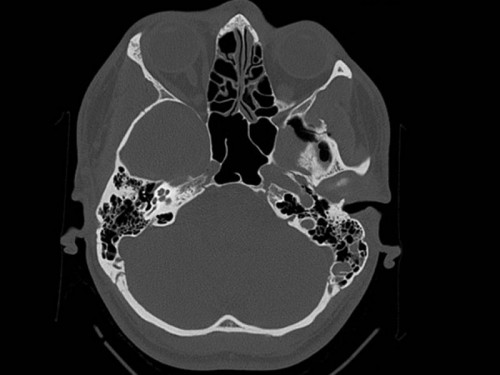

Ein 24-jähriger Student möchte mit seinem Skateboard einen schwierigen und sehr beeindruckenden Sprung ausprobieren, beachtet aber nicht, dass der Asphalt noch regennass ist. Das Skateboard rutsch unter seinen Füßen weg. Der junge Mann kommt schwer zu Fall und schlägt mit dem Gesicht auf dem Boden auf. Seine Freunde berichten, dass er für ca. 1 Minute bewusstlos war. Er selbst kann sich an nichts mehr erinnern.

Bei der Untersuchung in der Notambulanz fällt ihm auf, dass etwas Flüssigkeit aus seinem linken Nasenloch herausläuft.